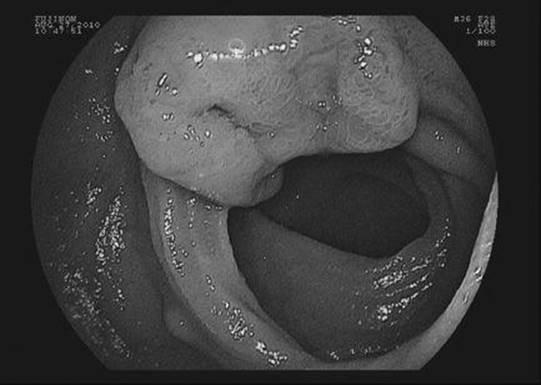

True/False: Small bowel carcinoids commonly present with gastrointestinal bleeding.

Figure 23-1 See also color plate.

False. Gastrointestinal bleeding from ulcerated tumors as shown in the figure is uncommon. Intermittent obstructive symptoms are more common. Presentation with the carcinoid syndrome is rare.